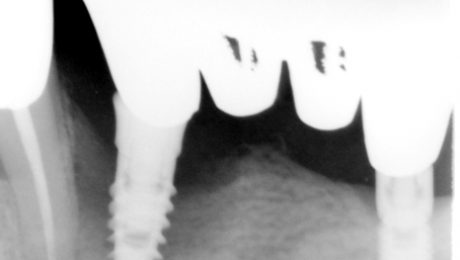

Al paziente viene rimosso un precedente impianto non bene integrato. Si procede a curettage alveolare, innesto di osso bovino denaturato ricoperto da una membrana in goratex con rinforzo in titanio. Una volta rigenerata la quantità ossea voluta si è proceduto all'inserzione di due impianti.